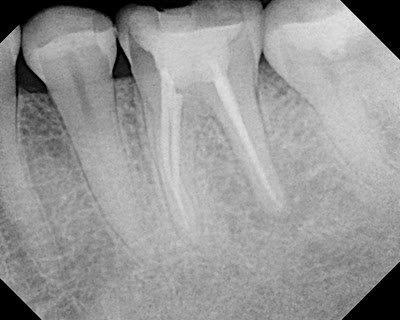

This patient came to our office today for consultation. Pt reports that RCT was done many years ago without any issues. Last year he traveled to Mexico for some dental work. The crowns were placed on #30 & #31. A periapical lesion has now developed on the mesial root of #30. My diagnosis is: prior RCT w/ symptomatic apical periodontitis. Coronal leakage is identified radiographically on mesial and distal margin. In this case, you could easily say the root canal failed. However, the inadaquate coronal seal on #30, in my opinion, is just as likely the cause for the periapical lesion on the MB root.

In our practice at Superstition Spring Endodontics, we would diagnose #30 as: Prior RCT with SAP (symptomatic apical periodontitis – percussion pain) with coronal leakage. Retreatment would be recommended. We would explain to the patient that for long term success, we need to prevent any leakage from above. (We would also recommend evaluation of mesial margin #31 by general dentist)